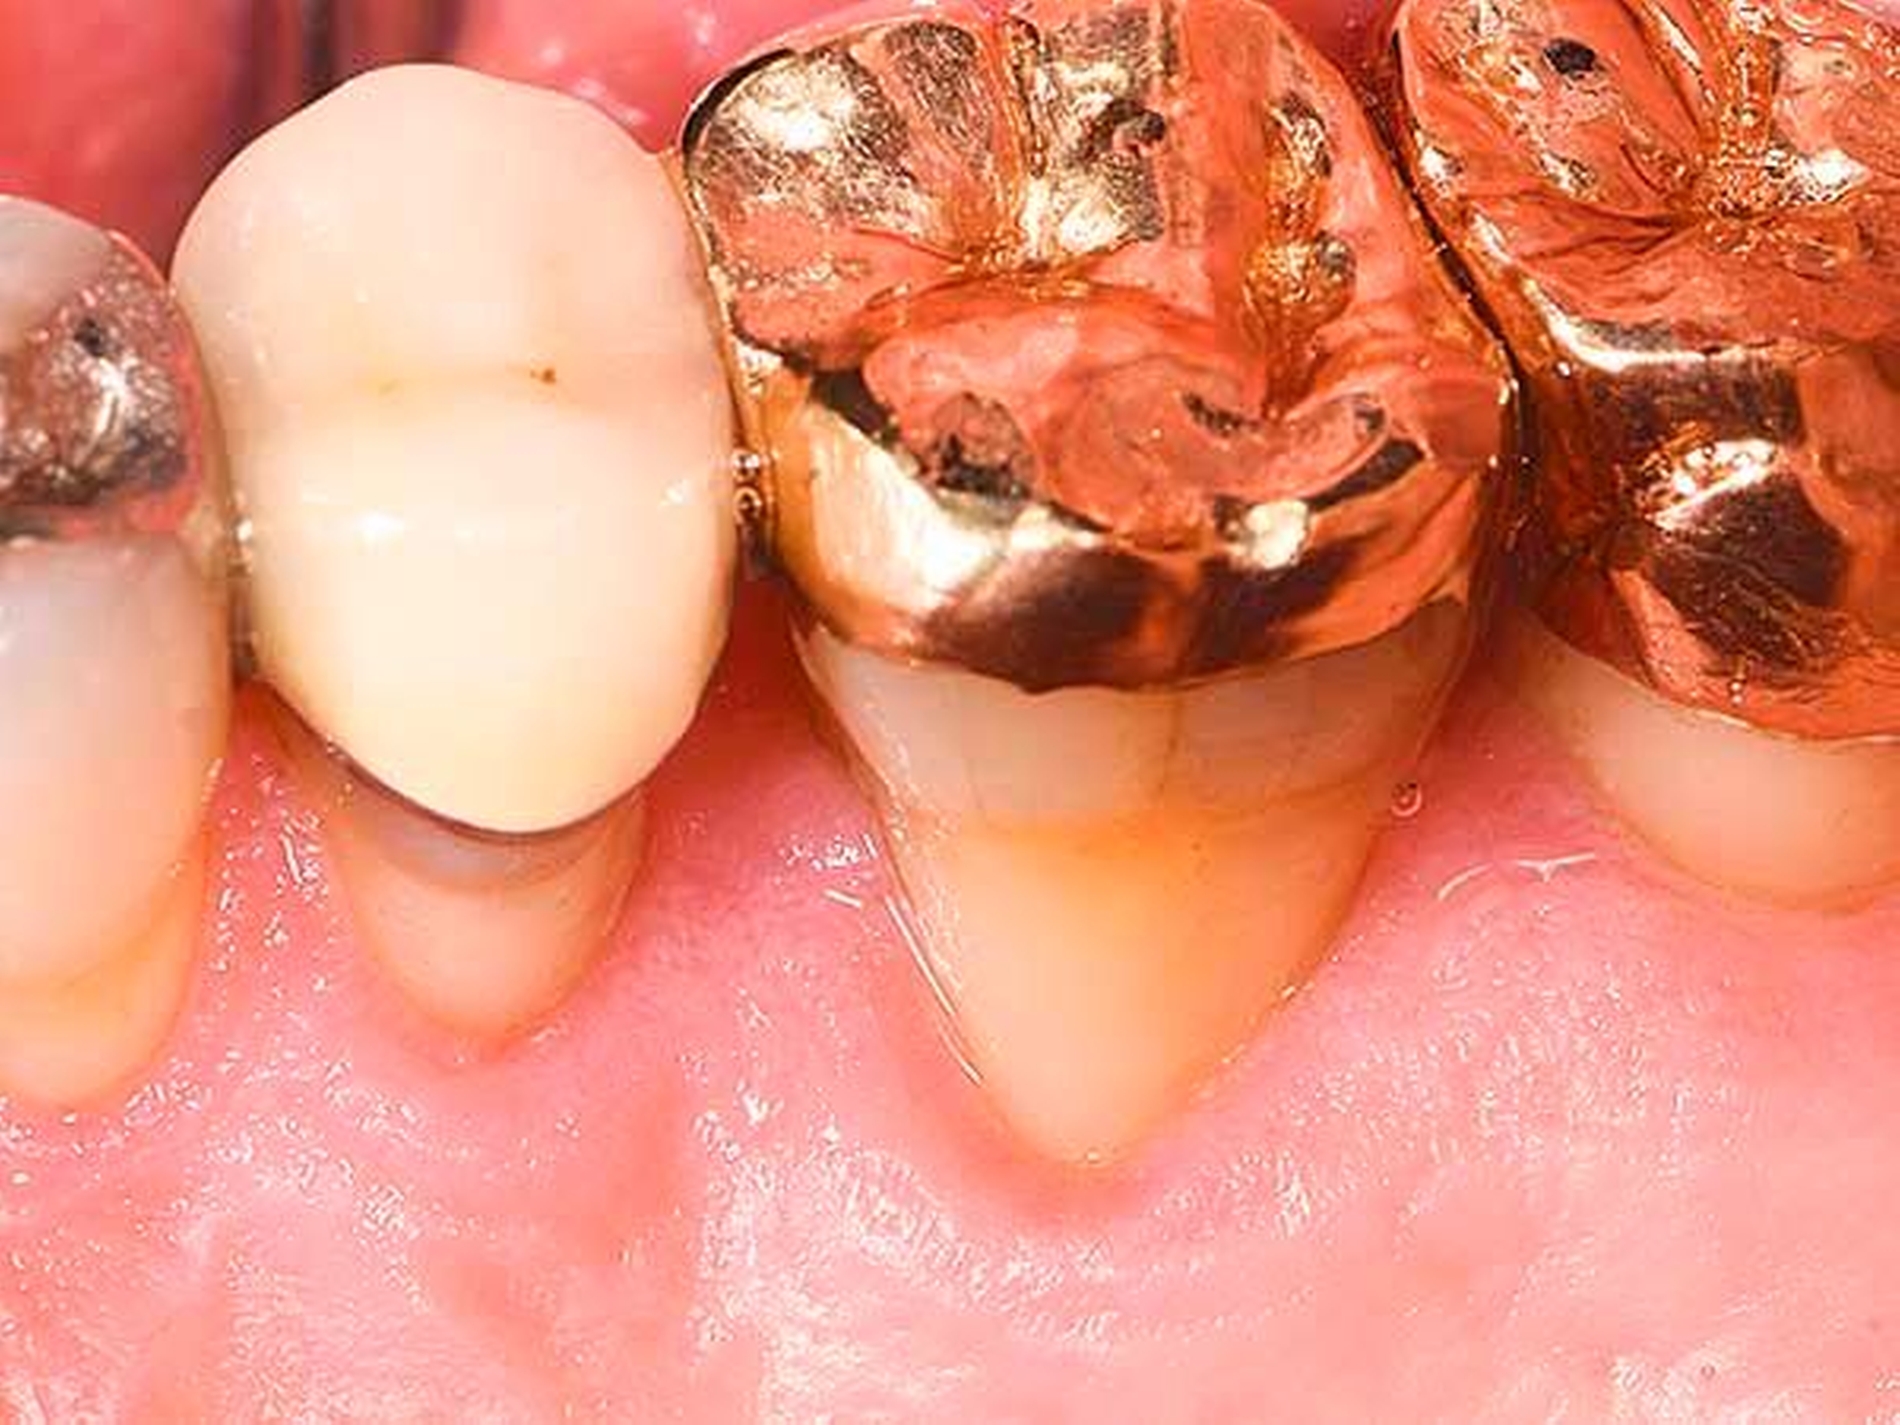

Eine klassische, sehr effiziente und vorhersagbare Möglichkeit der Adressierung von Resttaschen nach der ersten Therapiephase ist die resektive Parodontalchirurgie (Abbildung 5). Mittels eines apikalen Verschiebelappens mit resektiver Knochenchirurgie wird eine positive Gingivaarchitektur mit minimalen Sondierungstiefen auf reduziertem Niveau erschaffen [Carnevale und Kaldahl, 2000; Kebschull und Dommisch, 2013]. Diese Therapieoption wird aufgrund der ästhetischen Einschränkung durch starke Gingivarezession nur in der funktionellen Zone oder präprothetisch (zur Kronenverlängerung) durchgeführt. Die resektive Chirurgie ist bei tiefen Resttaschen ohne einer regenerativen Therapie zugängliche Defekte (siehe unten) indiziert.